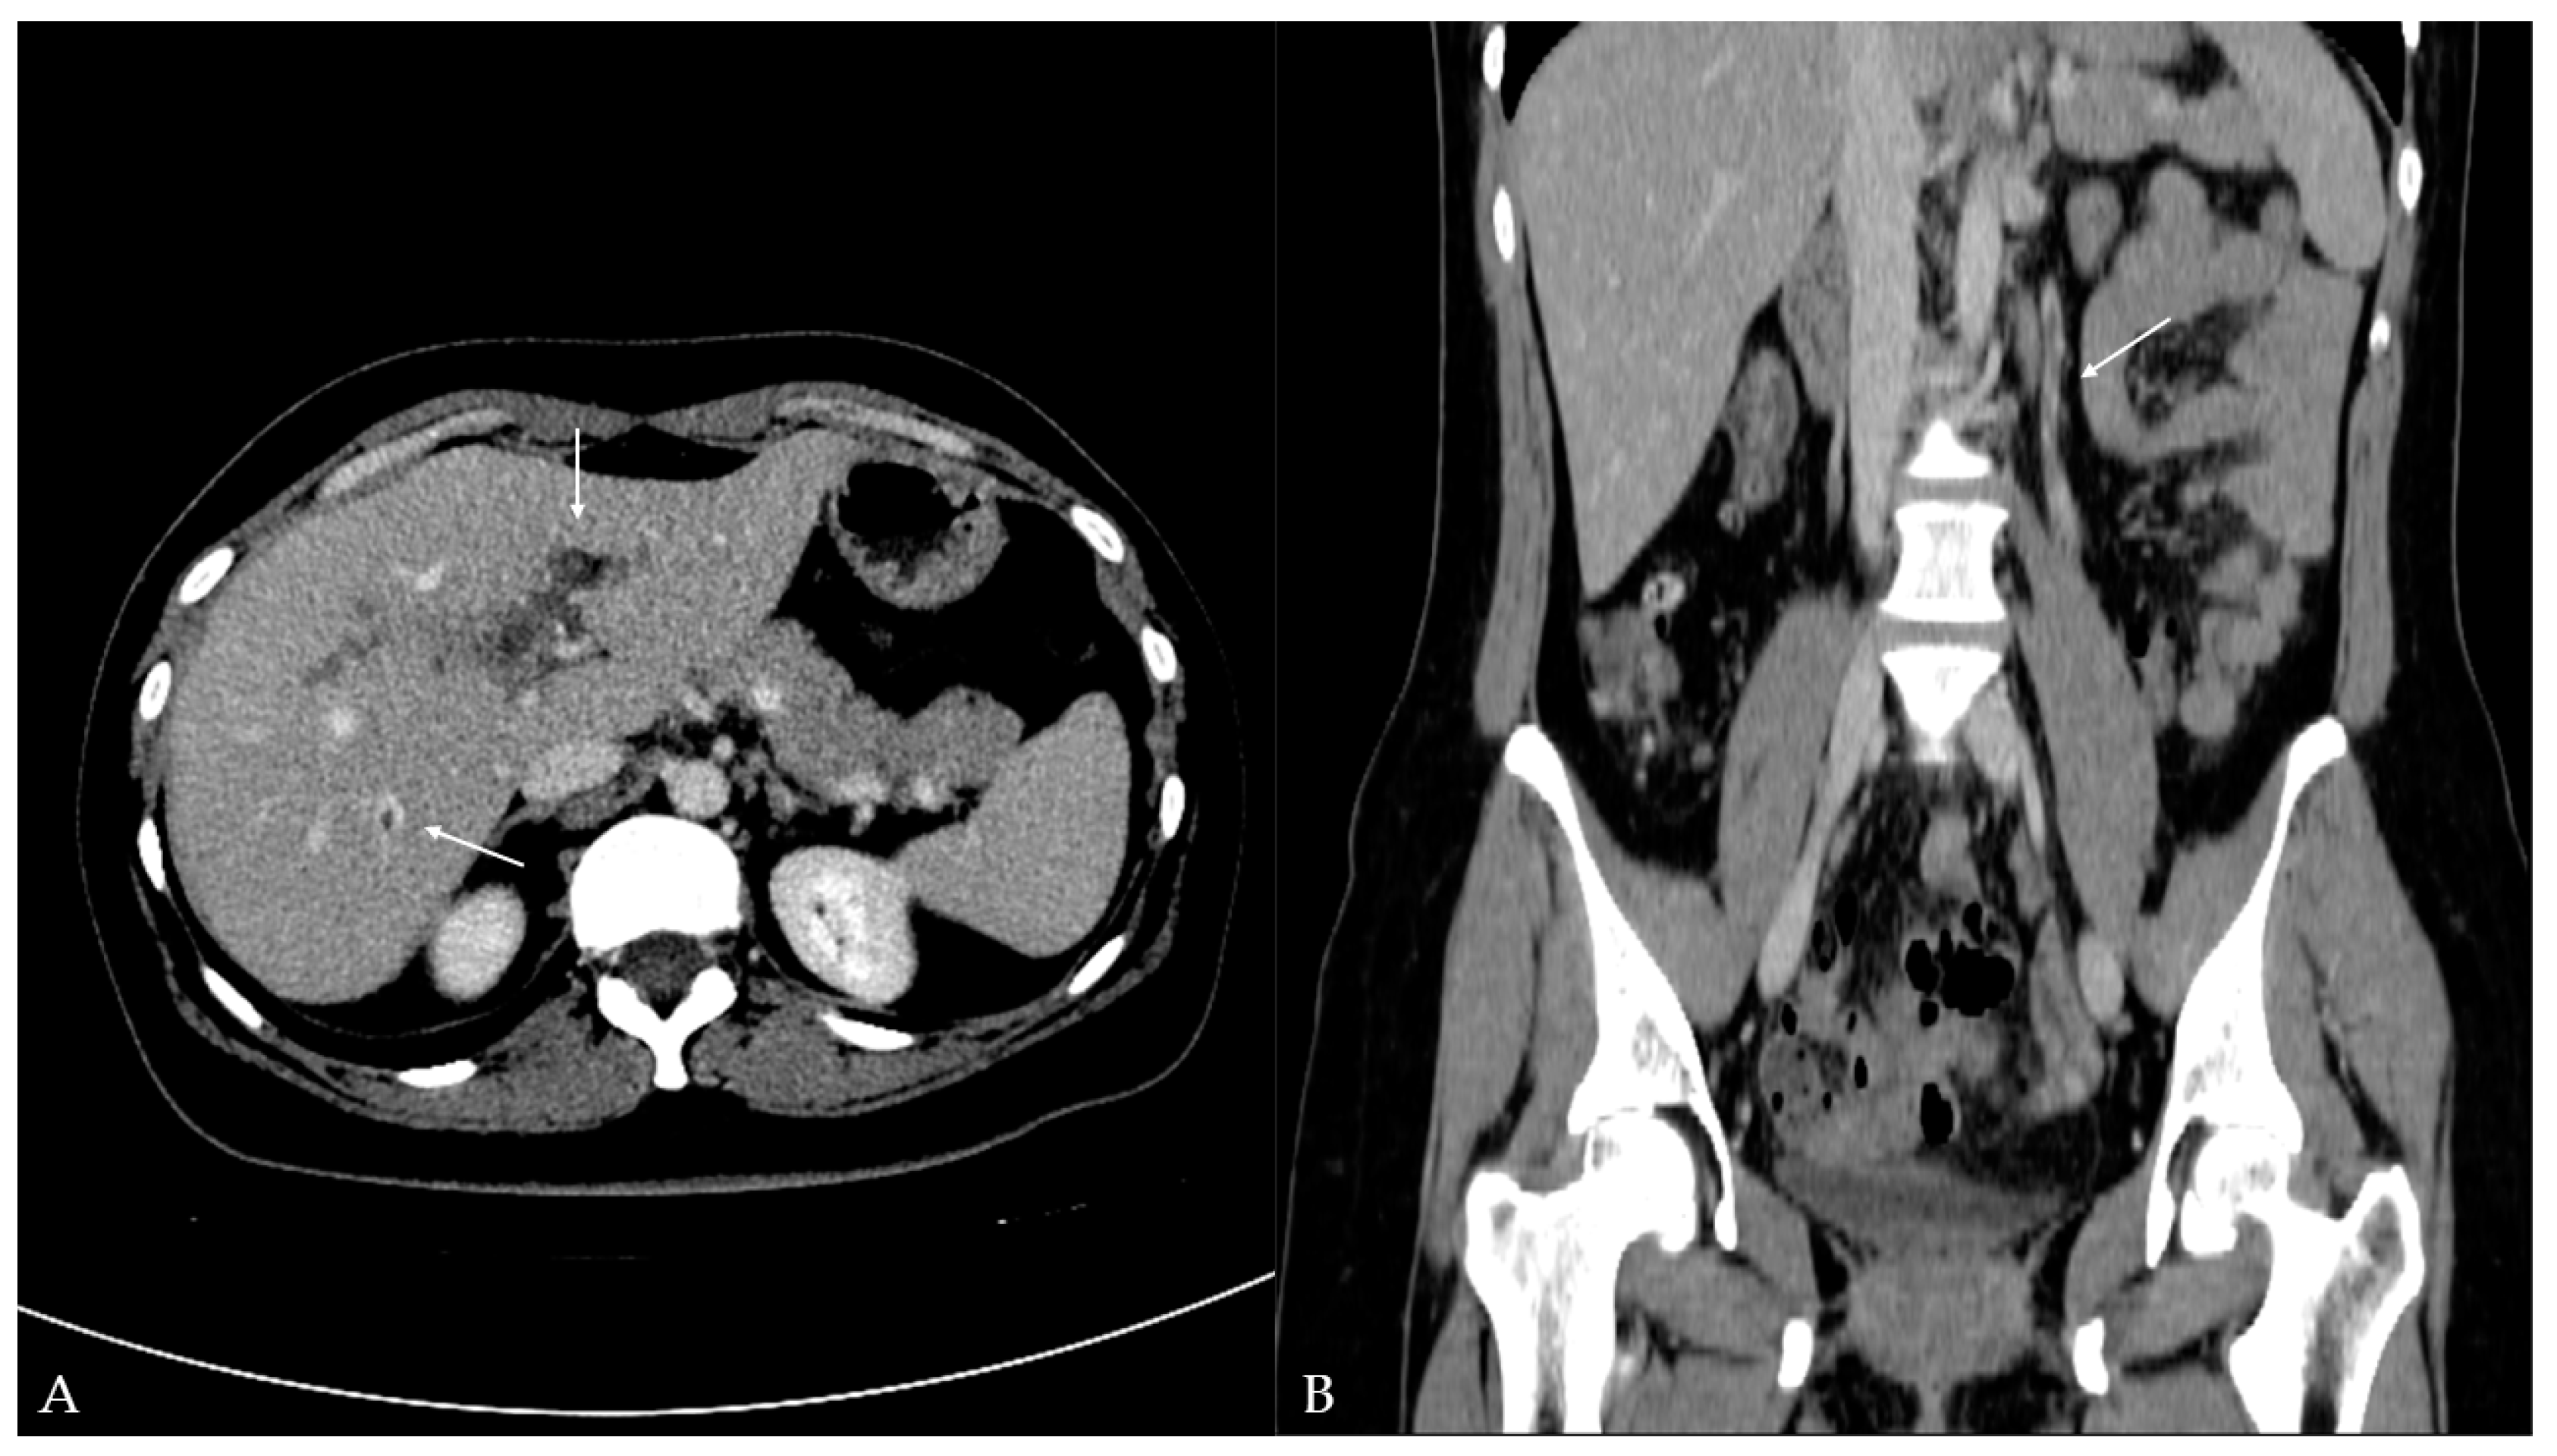

Twelve days later, the patient presented to the ED with a two-day fever (38 °C) and no other symptoms. The postoperative scar and ileostomy were unremarkable, and no signs of peritonitis were detected on clinical examination. Laboratory blood tests showed leukocytosis [15.56 (3.4–9.7 × 109/L)] with neutrophil predomination [10.99 (2.06–6.49 × 109/L)] and elevated liver enzyme [AST 63 (11–34 U/L), ALT 153 (8–41 U/L), GGT 220 (9–35 U/L), ALP 185 (54–119 U/L)] and CRP levels [99.6 (<5 mg/L)]. Other parameters were within the normal values. The attending surgeon referred the patient to the transabdominal US under suspicion of fluid collection. The US and color Doppler (CD) analysis showed left portal vein thrombosis and preserved patency of the hepatic arteries, veins, and inferior vena cava (Figure 1). No free fluid or collection was found. The patient was then referred to contrast-enhanced abdominal and pelvic CT to evaluate the extent of the thrombosis (Figure 2). The left branch of the portal vein was occluded entirely, and the segmental branch of the right portal vein was partially occluded. Thrombotic content was also found in the inferior mesenteric vein. No free fluid, collection, or liver and bowel perfusion abnormalities were found. Due to the described findings and recent diverticulitis, pylephlebitis was the imaging diagnosis. The patient was admitted to the hospital and put on low-molecular-weight heparin (LMWH) and intravenous administration of antibiotics (meropenem).

Figure 2. Contrast-enhanced computed tomography of the abdomen and pelvis: (A) axial plane—hypodense filling defects (thrombus) in the left portal vein and additionally in the segmental branch of the right portal vein (arrow); (B) coronal plane—additional hypodense filling defects (thrombus) detected in the inferior mesenteric vein (arrow).